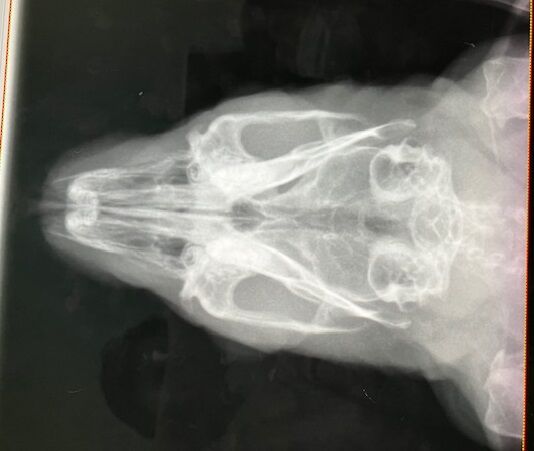

術前検査のレントゲン

特に問題ありません。

※クリックで拡大見れます。

切歯もキレイ